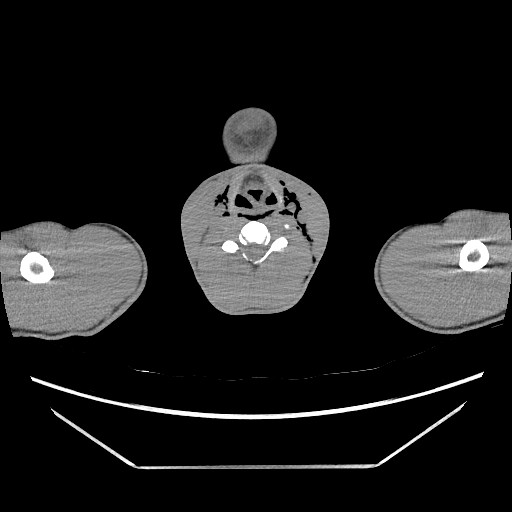

TAC: neumomediastino anterior, medio y posterior. Enfisema subcutáneo cervical izdo. Posible perforación esofágica tras ingesta de contraste. No neumotórax ni neumoperitoneo.